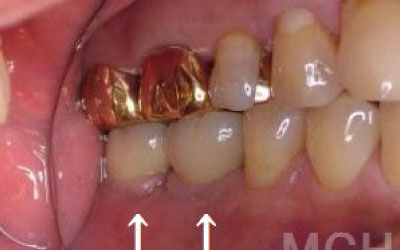

しばらくすると、抜けたままでも慣れてしまうことがありますが、その後に大きな問題が生じることがあります。

1 周囲の歯が早く抜ける

抜けた歯にかかるはずだった噛む力が、知らず知らずのうちに他の歯に負担をかけてしまいます。その結果、残っている歯が突然折れてしまい、抜歯が必要になることがよくあります。

2 歯が傾いてくる、落ちてくる

歯は互いに支え合い、バランスを保っています。そのため、歯が抜けると支えがなくなり、抜けた部分の両隣の歯が傾いたり、上の歯が下に移動してきたりすることがあります。